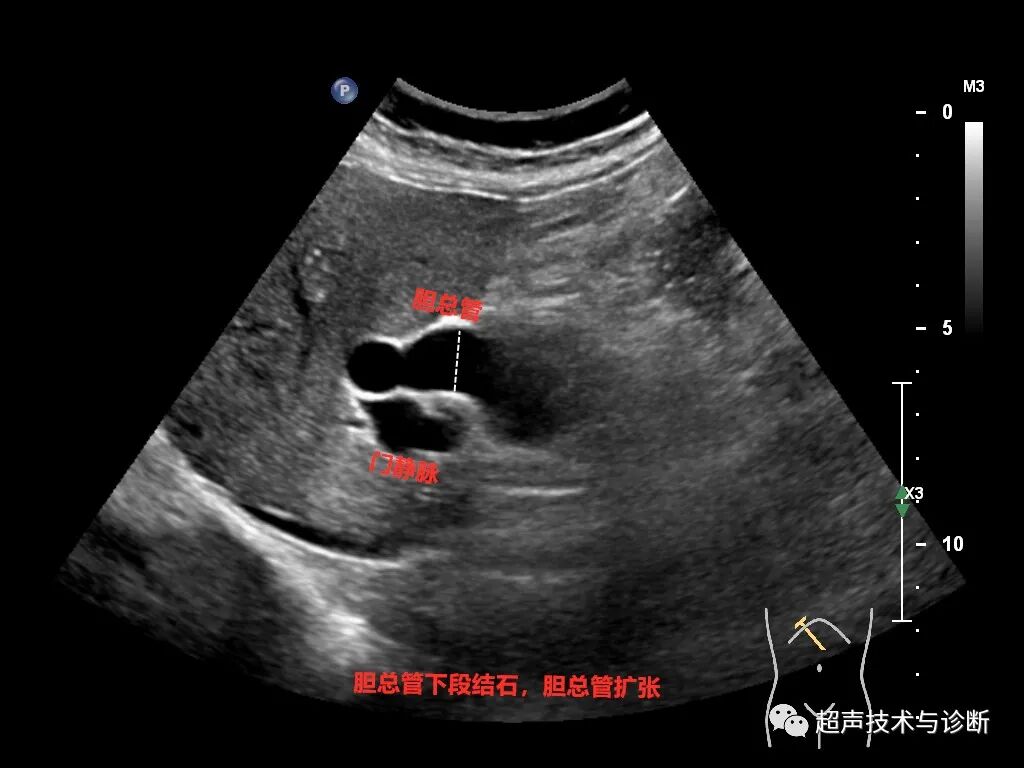

③ 胆总管或肝外胆管下段:先显示胰腺长轴切面,在胰头后外方寻找胆总管胰头段短轴图像,再旋转探头显示胆总管下段长轴切面。

① 正常成人肝外胆管最大内径<8mm,可随年龄增长而增宽,65岁以上正常人最大内径可达10mm。